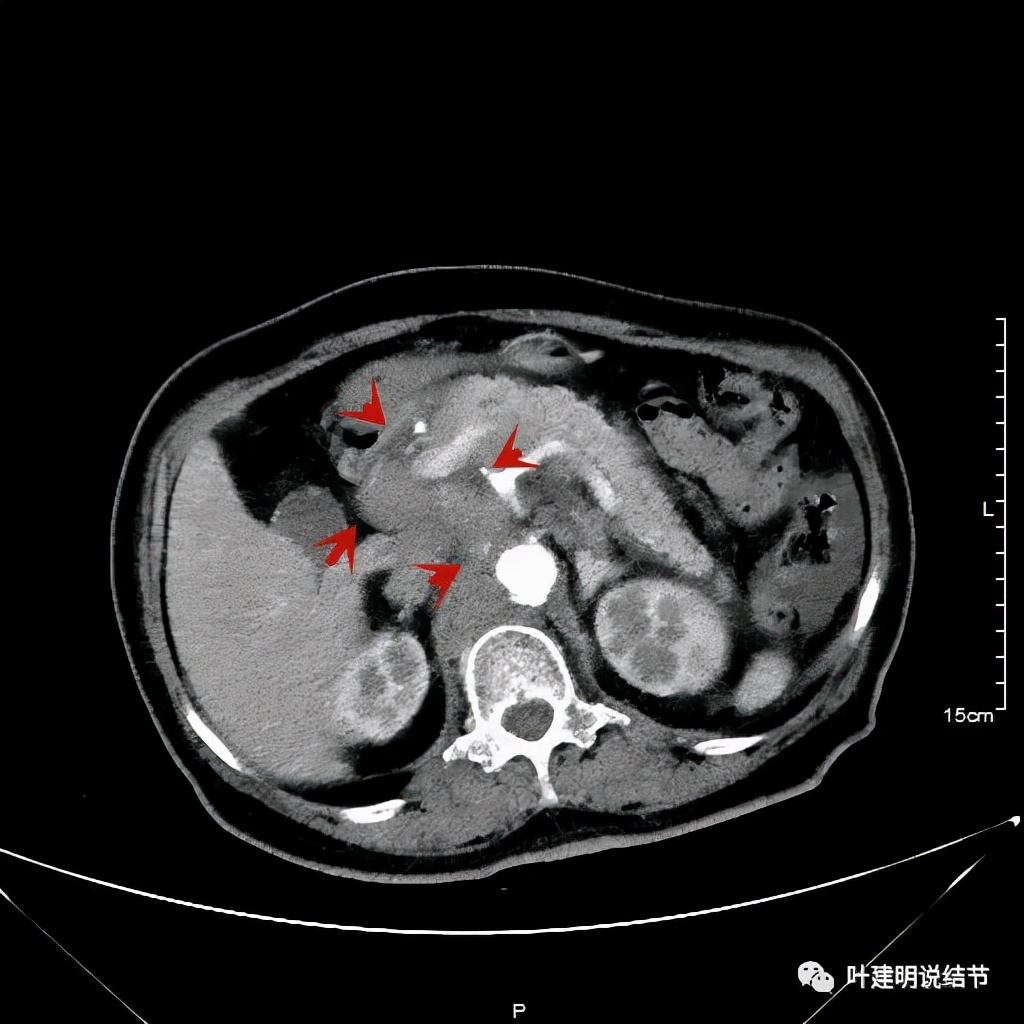

我们选择了“特瑞普利单抗加多西他赛加卡铂”的化疗加免疫治疗方案。我们来看经过一个周期治疗后肿瘤改善情况的对比:

上图左侧是治疗前的,右侧图像是差不多同一层面(因原肿瘤挤压,很难完全找出同一平面),可见病灶明显缩小改善了!下面是复查时的CT影像报告: